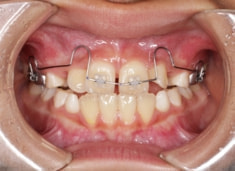

治療法:上顎急速拡大装置+クリアスナップ+フェイスマスク+上顎3番は開窓牽引CT写真にて位置確認

治療開始時